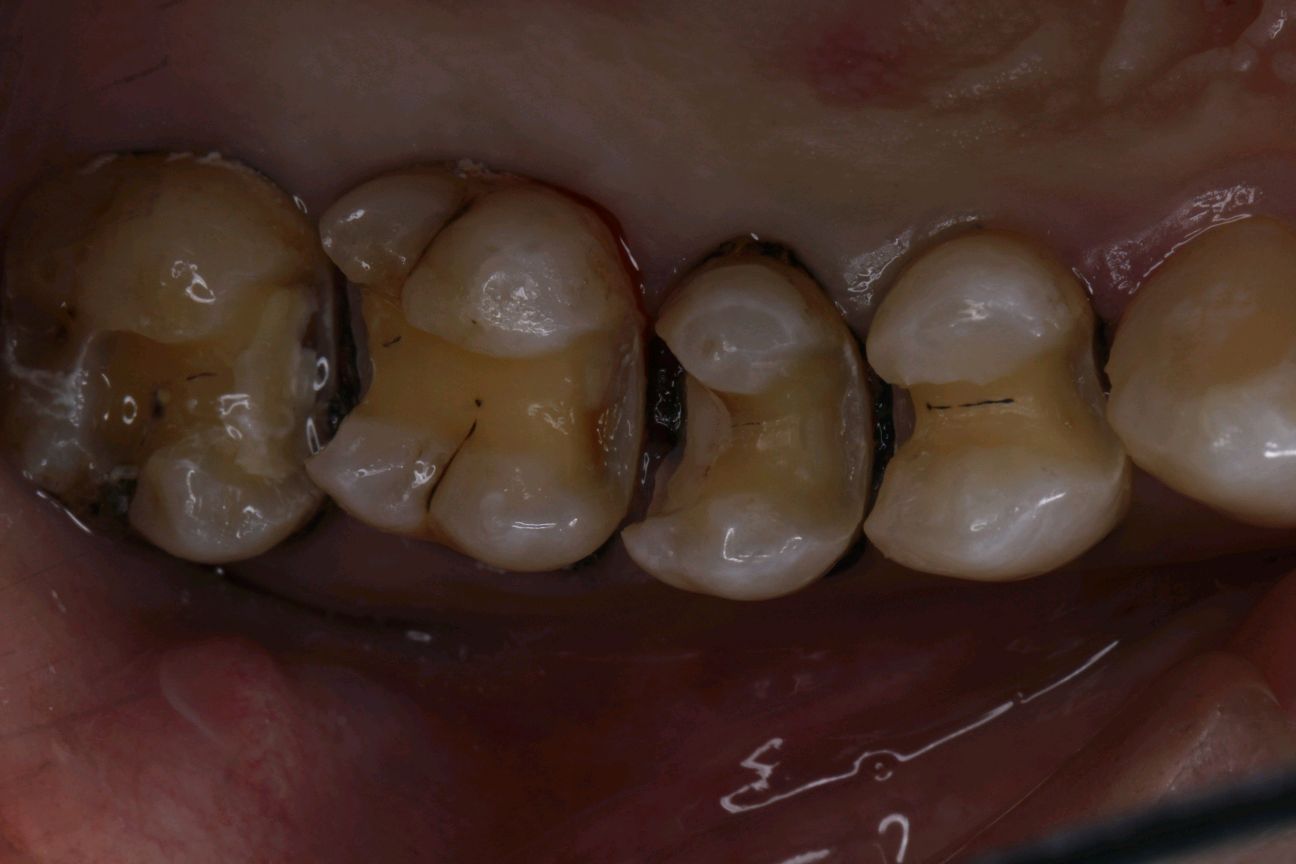

术中